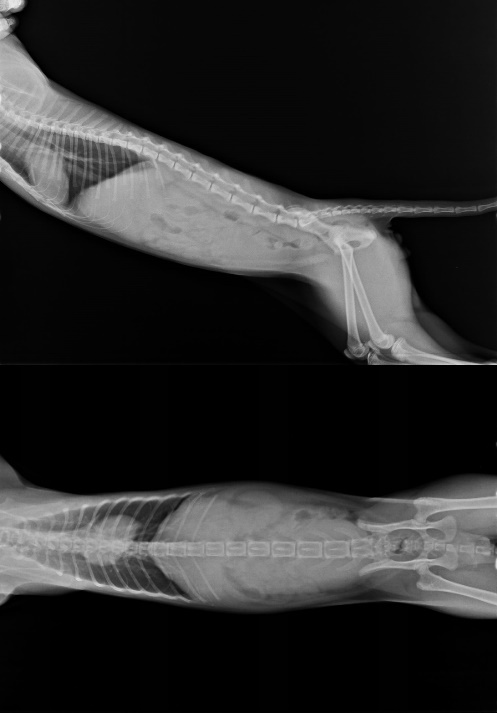

主題: 身體孱弱的小王子 申請者姓名: 臺北市支持流浪貓絕育計劃協會 花色: 申請日期: 2014-06-06 17:03:00 申請者部落格: 申請者臉書網址: 所在縣市/合作醫院: 台北市/極光動物醫院 治療費用: 15790元 需求人數: 17人 已結案 (2014-07-02 17:29:13) 報名人員: Sunny Chen x3(已付款)、葉姿纓(已付款)、米偷(已付款)、iMADOKA(已付款)、shuku點點(已付款)、Rebecca Chen(已付款)、斑比(已付款)、Candice Chao、蕭孟珣 x2(已付款)、WeiLin Chen x2(已付款)、Annie Cheng(已付款)、Bubu Wang(已付款)、小四(已付款)、叮叮(已付款)、 候補人員: 動物病情說明: 全身蒼白精神不佳的小王子,由志工捕捉送醫治療,在安養之家等待幸福,某日小王子的罐罐和飼料都沒有吃,精神不佳,軟趴趴的,緊急送醫,體溫40度,發燒、眼膿鼻淚水嚴重不肯進食,上點滴幫助退燒,給予口服抗生素治療,五天後狀況稍微穩定,拆點滴觀察一天狀況穩定,帶回協會繼續噴物治療、餵食,醫療費用還請各位幫忙。